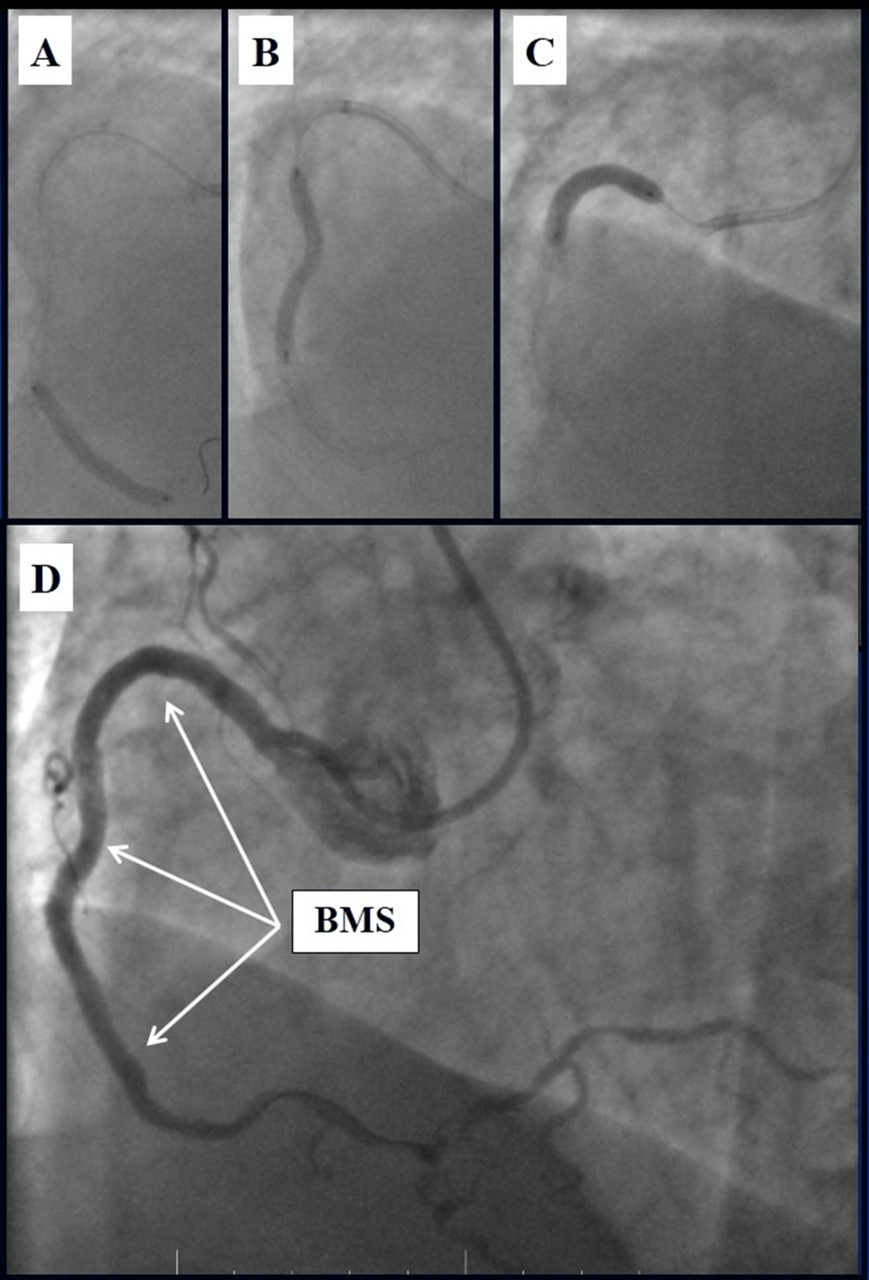

Due to financial problems the second stage was performed after 3 months (during this time the patient solved his financial problems). CAG revealed patent stents in LAD (Figure 7), and 60-70% restenosis by BMS in RCA (Figure 8). In-stent restenosis was treated by plain old balloon angioplasty (POBA), the optimal result was obtained (Figure 9). After LMCA quadrifurcation balloon predilation, 2.5×26 mm DES (Resolute Integrity, Medtronic) was implanted in the IMA, using a modified balloon mini-crush technique. The stent was minimally protruded in the LMCA and its edge was crushed by preloaded MB balloon. Next 2.5×30 mm DES (Resolute Integrity, Medtronic) was implanted in OM1 through the CX (first marginal and circumflex arteries in this particular case have the same ostium). The stent was protruded in the LMCA as in conventional modified balloon crush stenting technique, after stent deployment, its balloon was pulled back and overinflated, then protruded stent was crushed by preloaded MB balloon (Figure 10). 3.5×15 mm DES was implanted in the LMCA so that distal part of the stent covered ostial and proximal segments of the LAD. Sequential post-dilatations were performed using a kissing balloon technique (1. LMCA-LAD-IMA,2. LMCA-LAD-CX-1OM). After post-dilatations, through the stent implanted in CX-OM1, coronary wire and smaller diameter balloon (2.0 mm) were advanced in direction of the CX mid-segment and by balloon dilatation stent’s strut was opened (provisional stenting technique for CX). Finally, the proximal optimization technique was performed in the LMCA using a 3.5 mm diameter non-compliant balloon (Figure 11). The final angiographic image was good, the intervention ended without complications (Figure 11, Figure 12). We could not confirm the result with IVUS or OCT due to several technical and financial problems (not covered by insurance). 1 month after PCI, at regular checkout, the ejection fraction was 48%, the functional class of the Congestive Heart Failure decreased from class II-III to class I and the patient complaints have been disappeared.

Figure 10.Stenting of the LMCA quadrifurcation: A, B - balloon modified mini crush stenting of the IMA, C - angiography result, D,E - modified balloon crush stenting of the CX-OM1, F - angiography result.

Stenting of the LMCA quadrifurcation: A, B - balloon modified mini crush stenting of the IMA, C - angiography result, D,E - modified balloon crush stenting of the CX-OM1, F - angiography result.

Figure 11.Stenting of the LMCA quadrifurcation: A, B – Stenting of the LMCA; C –Kissing balloon post dilatation of the IMA-LMCA-LAD; D - Kissing balloon post dilatation of the CX-OM1-LMCA; E, F - angiography result.

Stenting of the LMCA quadrifurcation: A, B – Stenting of the LMCA; C –Kissing balloon post dilatation of the IMA-LMCA-LAD; D - Kissing balloon post dilatation of the CX-OM1-LMCA; E,                             F - angiography result.